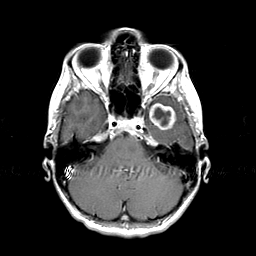

Metastatic bronchogenic carcinoma: T1-weighted MR -- Slice #5

[Home][Help][Clinical] Slice 5